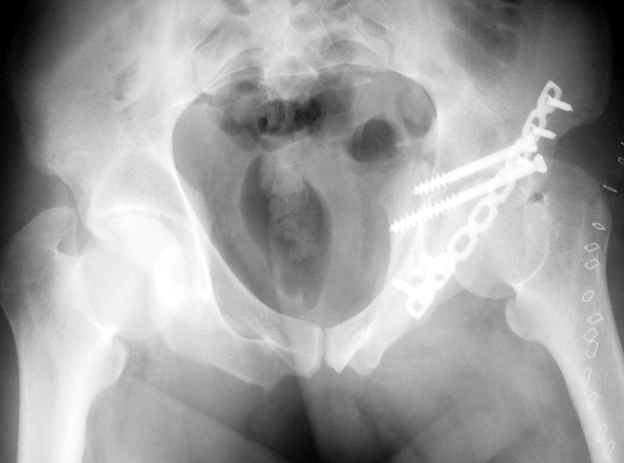

Не дождавшись советов, в понедельник прооперировал больного, заняло времени..., но все сделал в один этап: сначала фиксировал ипсилатеральный перелом бедра и шейки реконструктивным гвоздем Smith&Nephews, потом из расширенного илеофеморального доступа фиксировал перелом крыла подвздошной кости тягловым винтом, нейтрализующей пластиной заднюю колонну, и тягловыми винтами 3,5 мм переднюю колонну.

перелом крыла правой подвздошной кости, перелом обеих колонн вертлужной впадины, двусторонний перелом лонных костей (С2.2) повреждение передних связок правого крестцово-подвздошного сочленения,

ипсилатеральный перелом шейки и диафиза бедра.

К сожалению, набора для ретроградного или антеградного реконструктивного штифтования в операционной нет, поэтому доставка заняла н-ное время. Вопрос, который возник у меня- по поводу оптимальной тактики хирургии: вся фиксация в один этап из расширенного доступа или последовательно сначала бедро и позже реконструкция впадины, комбинированный доступ к впадине отдельно к передней и задней колоннам или из расширенного илеофеморального одного доступа. Все-таки решил остановиться на одноэтапном подходе и спустя 5 дней (как раз и наборы привезли) из расширенного илеофеморального доступа сначала фиксировал реконструктивным штифтом Smith&Nephews бедро и

шейку (благо перелом шейки 2 типа -относительно стабильный) затем фрагмент крыла подвздошной кости Lag screw, далее пластина на заднюю колонну и винты в переднюю колонну.(с размерами и направлением винтов ошибка вышла:-((, но интраоперационно у меня была полная уверенность , что винты *ушли* в лонную кость).

Еще раз спасибо за комментарии и готовность помочь с имплантами. Постоп картинки в приложении,